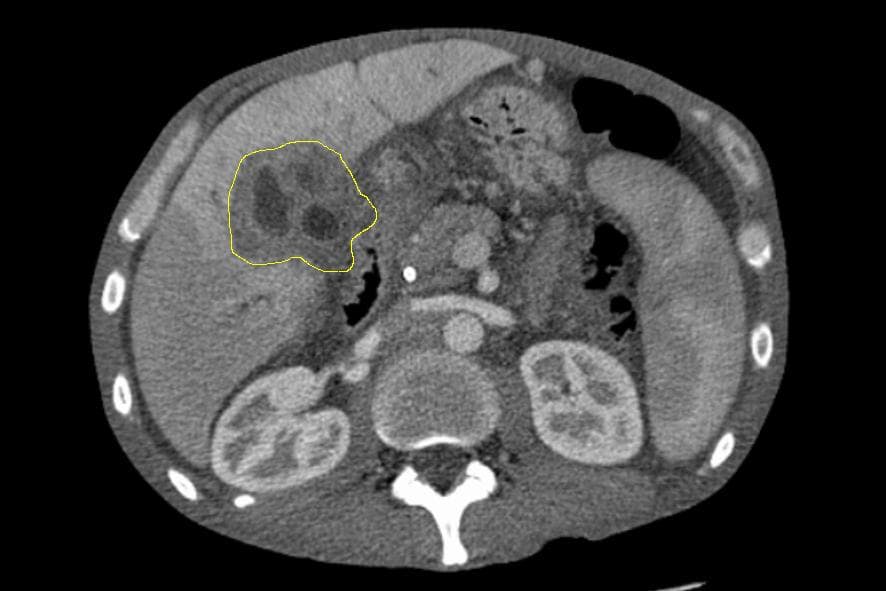

Le cholangiocarcinome (de chol du gr. χολή : « bile », angi(o) du gr. ἀγγαιον : « capsule, vaisseau » et carcinome du gr. καρκίνωμα : « cancer ») est une tumeur développée à partir de l'épithélium tapissant les voies biliaires. Il peut entraîner une obstruction des voies biliaires, et provoquer l'apparition d'une cholestase. Les symptômes cliniques sont essentiellement ceux provoqués par l'atteinte de la fonction hépatique. C'est un cancer relativement rare. Son pronostic est mauvais et son évolution rapide. Sa prévalence et la mortalité dont il est cause augmentent depuis quelques décennies sans que l'on puisse en déterminer les raisons. Les causes et facteurs de risques incluent des formes associées à des parasitoses (souvent en Asie du Sud-Est), les nitrosamines, les dioxines, le thorotrast (dioxyde de thorium en solution injectable), le radon et peut-être l'absorption d'amiante via la nourriture et/ou la boisson (alors notamment retrouvée dans le système digestif et des nodules cancéreux du système biliaire). Le traitement classique d'un cholangiocarcinome consiste en une ablation chirurgicale de la tumeur, un traitement par chimiothérapie anticancéreuse, voire en une approche palliative. vignette|Ictère cutané et conjonctival, dû à une augmentation du taux de bilirubine dans le sang et la peau. Les signes les plus courants de cholangiocarcinome sont une perturbation du bilan sanguin hépatique due à un fonctionnement anormal du foie (détectable lors du dosage notamment de la bilirubine, l'ASAT, l'ALAT, des phosphatases alcalines et de la gGT), un ictère (communément appelé jaunisse) s'accompagnant de démangeaisons (près de 66 % des cas), des douleurs abdominales (dans 30 % à 50 % des cas). On retrouve un changement de couleur des fèces qui se décolorent à cause de l'absence d'évacuation des sels biliaires vers le tube digestif. Ces derniers sont éliminés par l'urine qui devient alors plus sombre. Une altération de l'état général accompagne de nombreuses tumeurs comme le cholangiocarcinome avec fatigue, anorexie et perte de poids (dans 30 % à 50 % des cas).